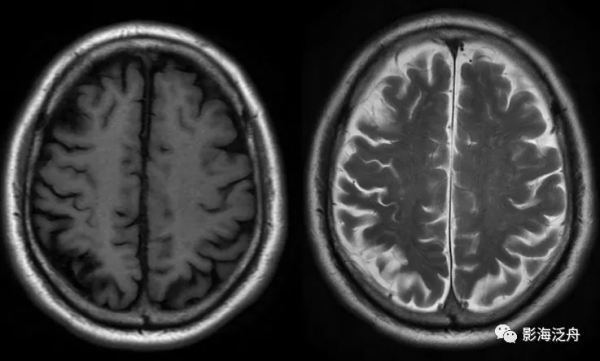

病例三:靜脈竇血栓。正常情況下,上矢狀竇在SE序列(T1WI)和FSE(T2WI)序列上均呈流空低訊號(綠箭頭),本例中上矢狀竇呈等高訊號(紅箭頭),結合患者頭痛病史,應考慮上矢狀竇血栓。